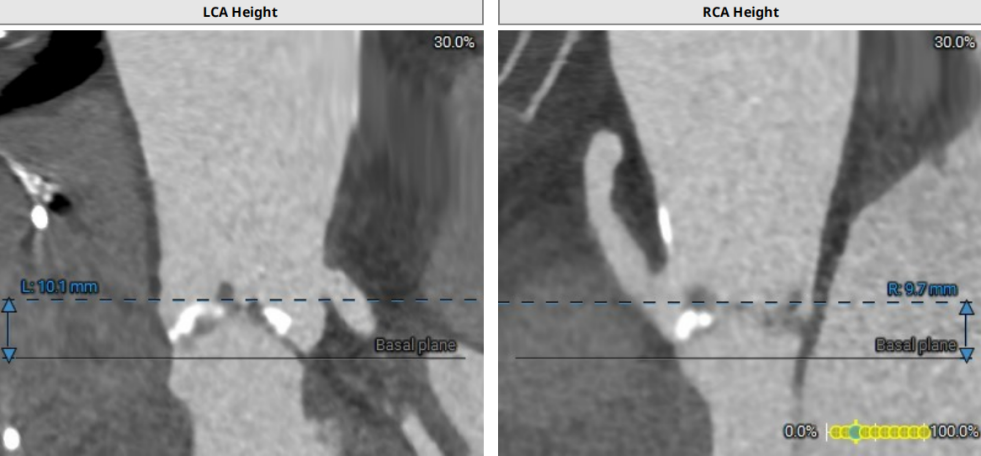

术前CT评估示

左侧冠状动脉开口高度10.4mm,右侧冠状动脉开口高度9.7mm。

升主动脉平均直径43.3mm,瓣上瓣下均有钙化。